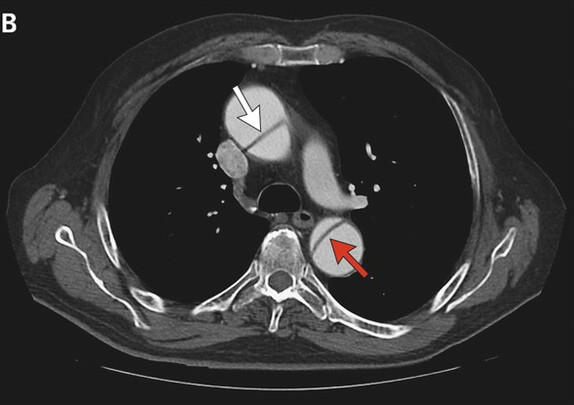

主动脉夹层

透析患者的主动脉容易发生硬化,是发生主动脉夹层的高危人群。主动脉夹层是由于在高压血流冲击下,主动脉内膜被撕裂,血液灌入内膜和中膜之间,导致血管形成假腔,甚至形成夹层动脉瘤,一旦破裂会引起致命性大出血。